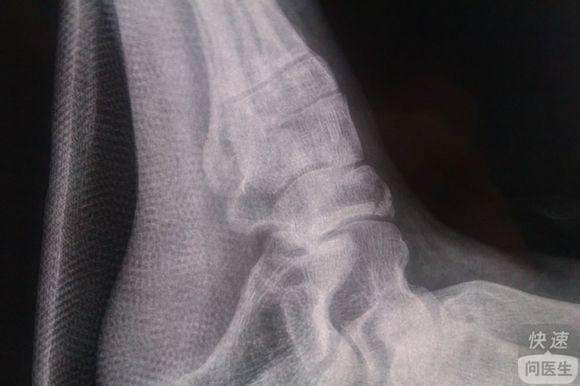

人体的各个部位都有骨骼的存在,骨骼的健康对保障人体活动有着重要的意义。人体的每一块骨头都发挥着重要的作用,其中足舟骨位于脚掌部位,若是出现损伤,会影响行动。足舟骨骨折给患者的生活造成了极大的困扰,人们需要增加...